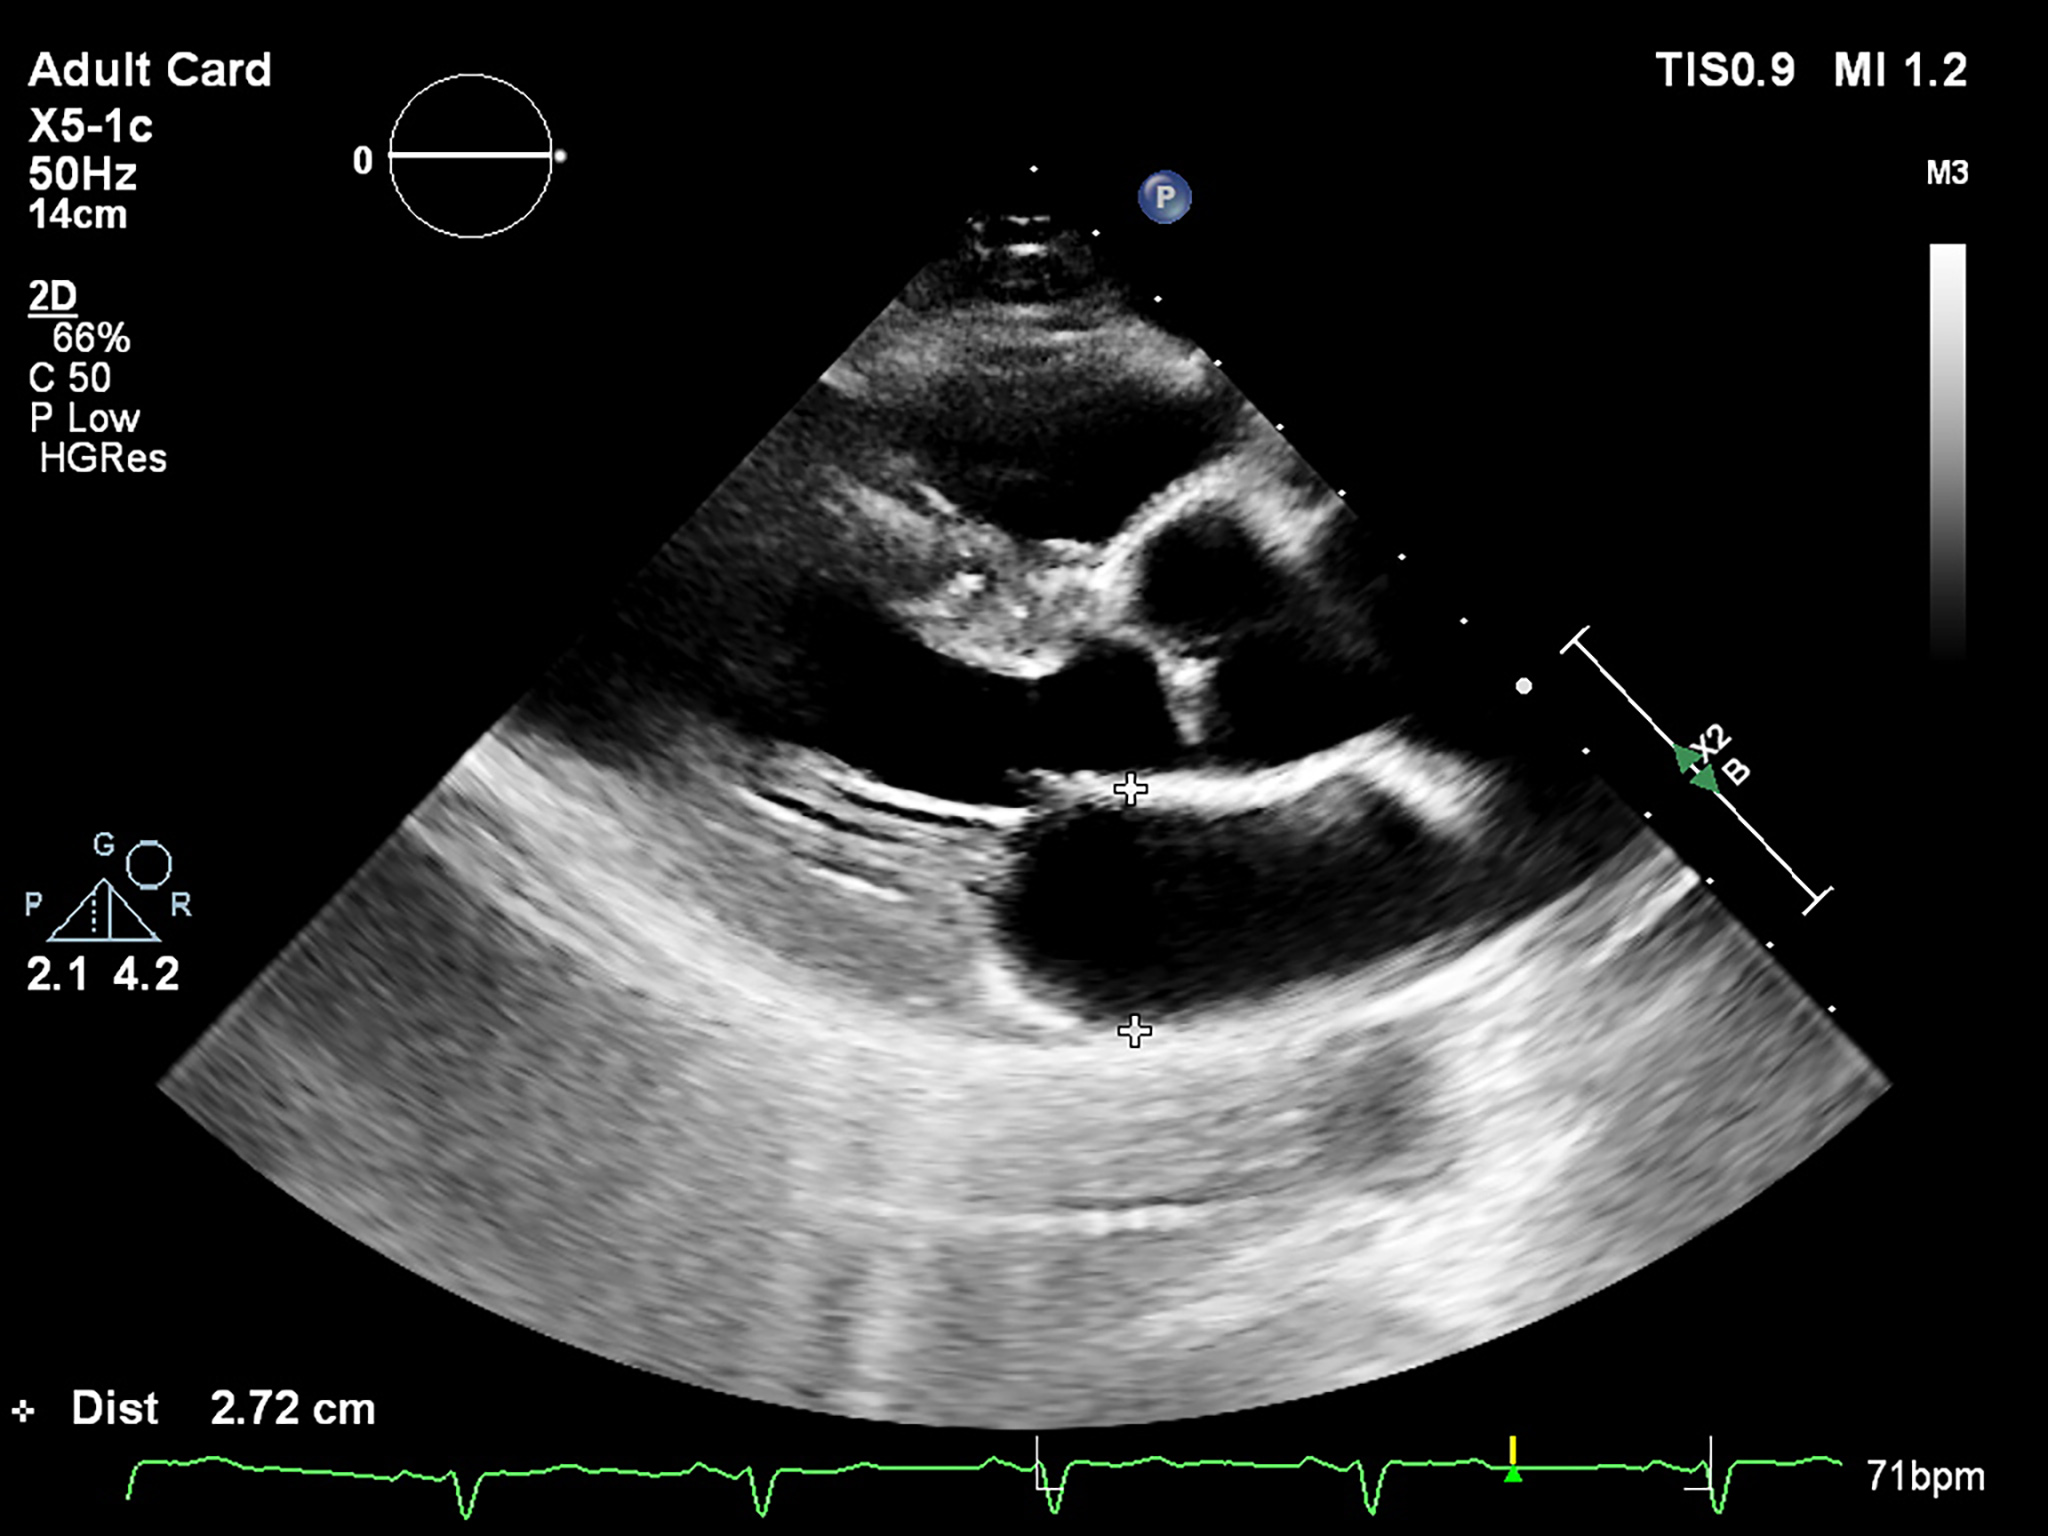

The LA antero-posterior (AP) diameter is the most evaluated parameter in patients with AF. The recommended measurement technique uses the long-axis view in bidimensional echocardiography (2D-E), perpendicular to the LA posterior wall, from inner edge to inner edge (Fig. 1). The latest chamber quantification recommendations suggest that the M-mode evaluation should no longer be used. The LA AP diameter was intensely evaluated in relation to AF development. An increased diameter, with a cut-off value of 40 mm, was associated with a higher risk of AF [22, 23]. This diameter should not be used solely, as it doesn’t represent the true LA size [24]. Moreover, the latest statements define a normal LA AP dimension less than 40 mm in males and 38 mm in females, with an indexed value of less than 23 mm in both genders [24].

Fig. 1.

Fig. 1.Measurement of the LA diameter (end-systole, inner edge to inner edge) in the parasternal long-axis view by bidimensional echocardiography.